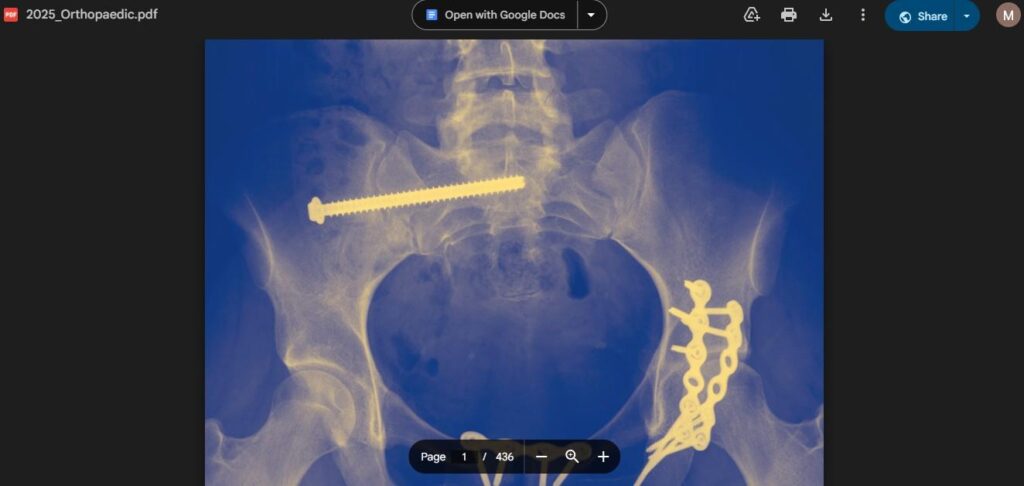

| Title | Orthopaedic Trauma: The Stanmore and Royal London Guide |

| Author | Sebastian Dawson-Bowling, Pramod Achan, Timothy Briggs, Manoj Ramachandran |

| Subject | Orthopaedic Trauma Management |